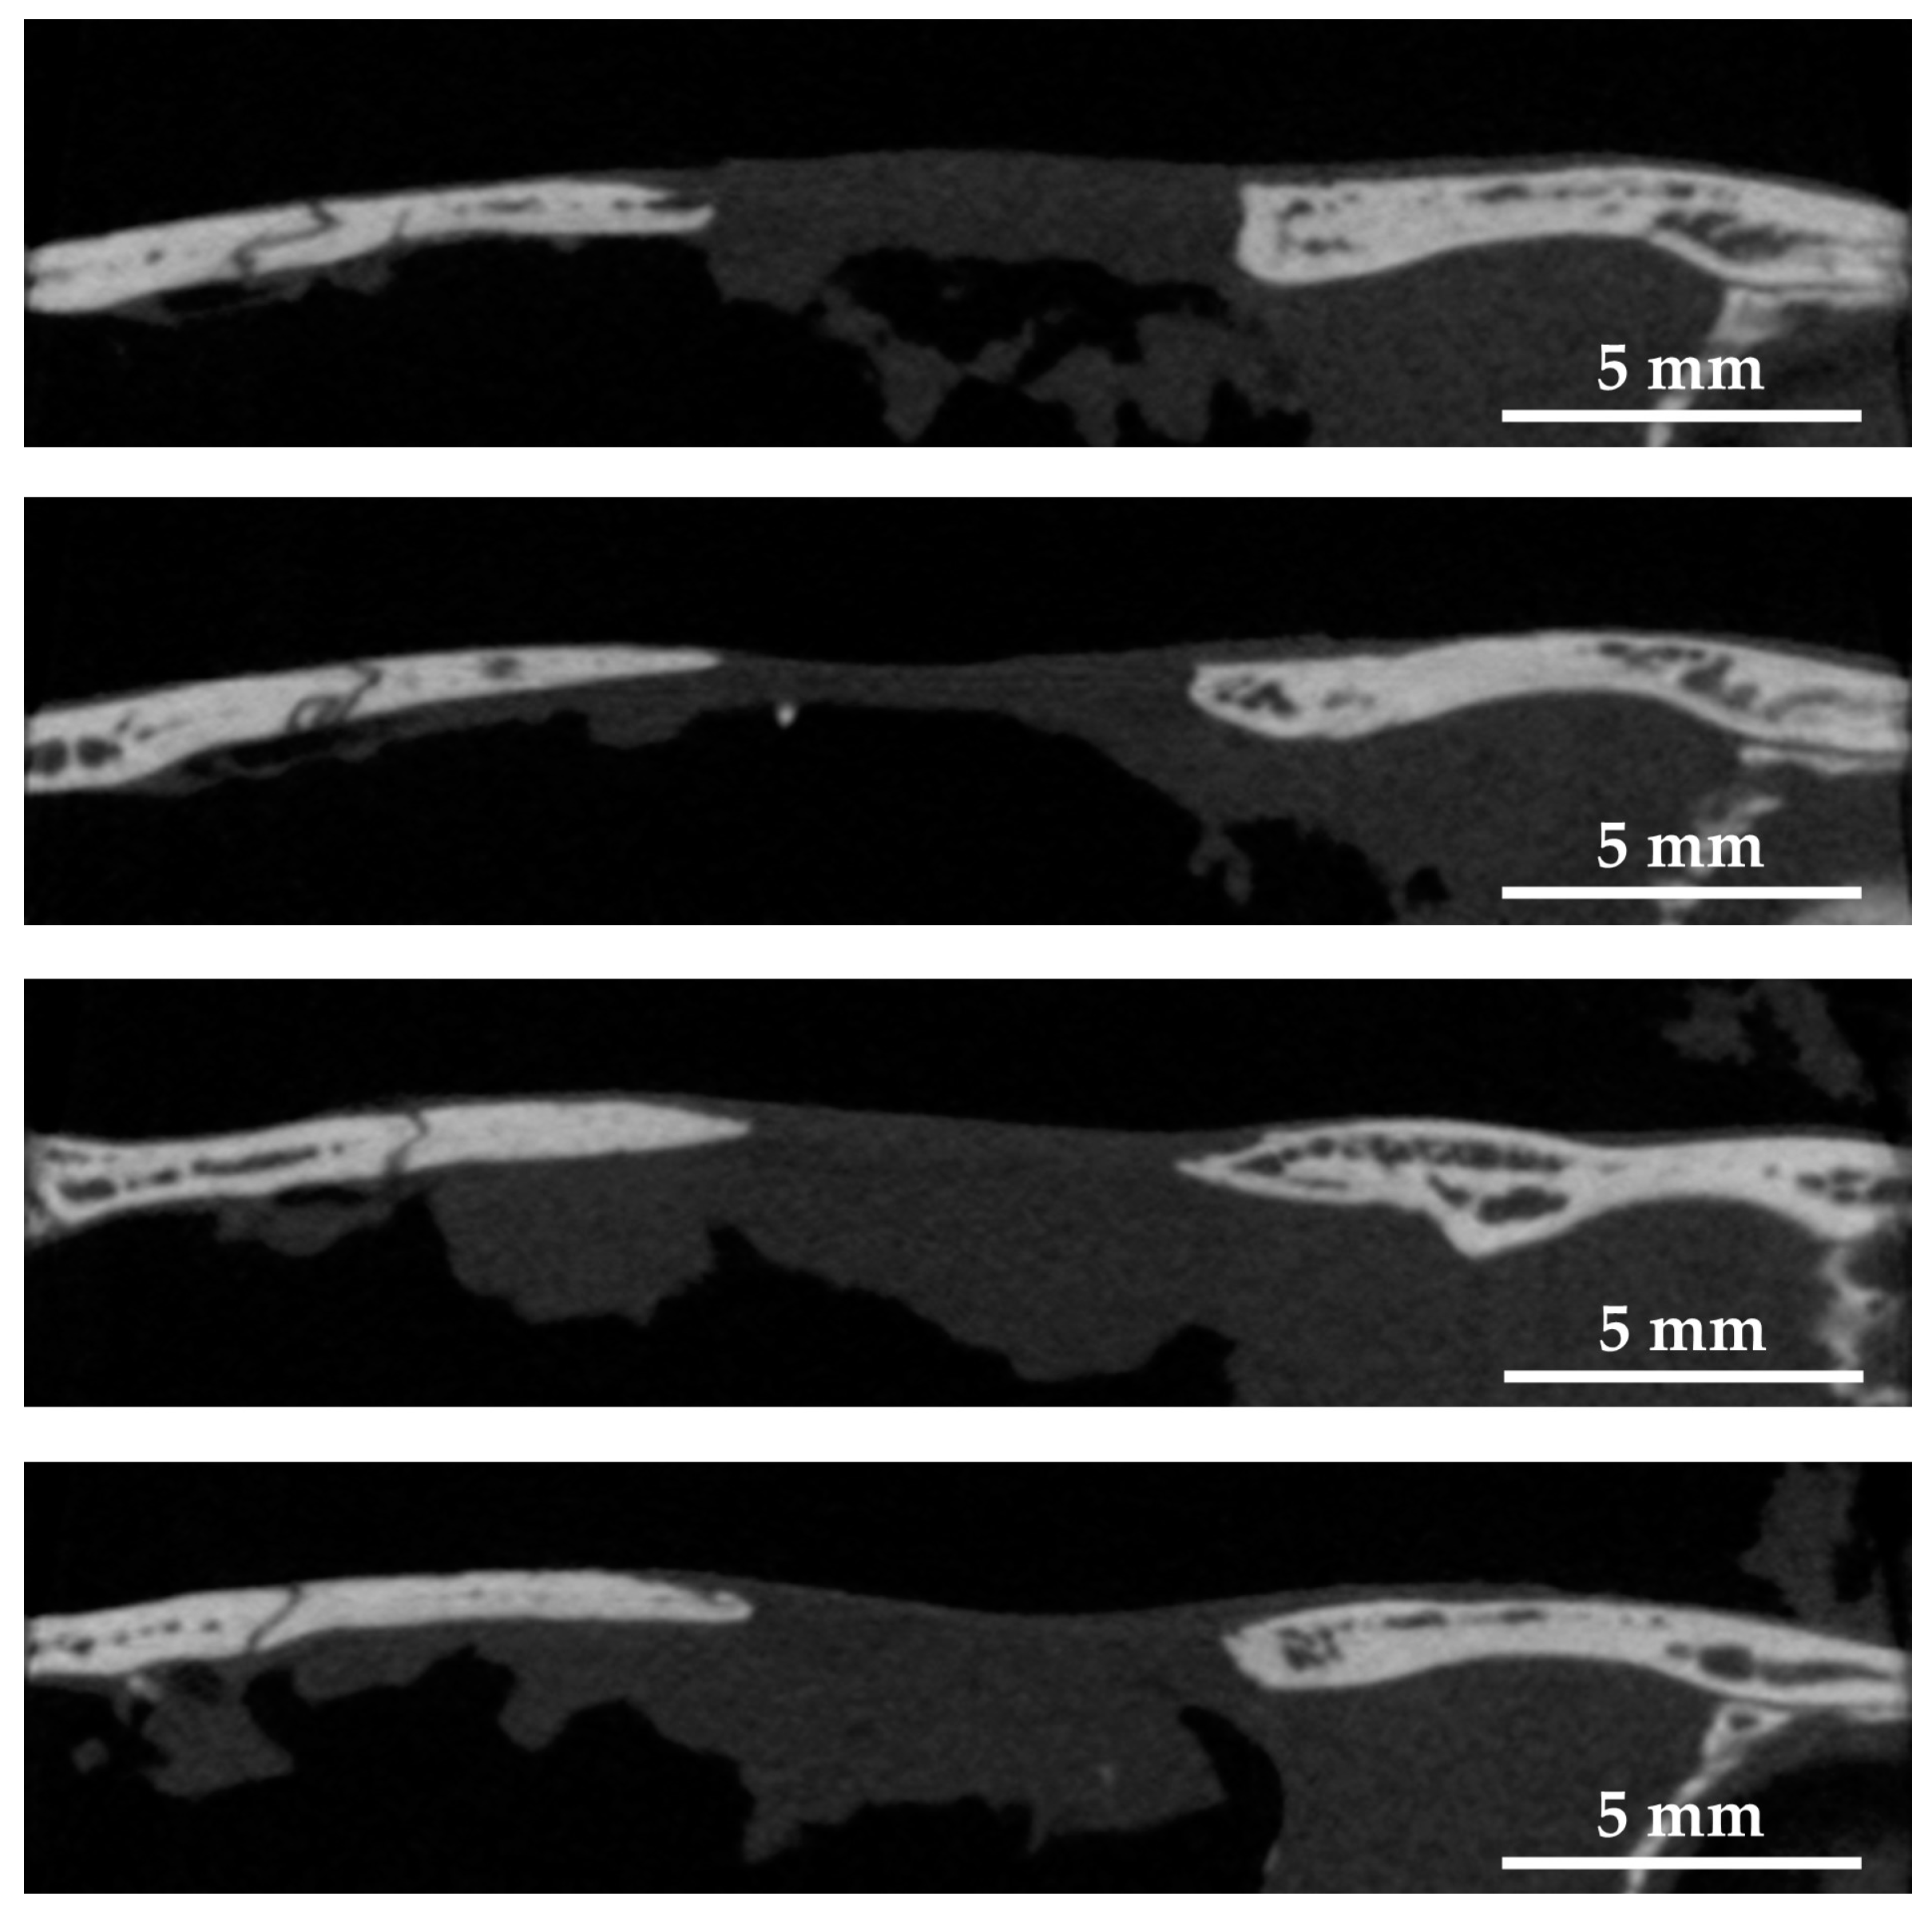

Figure 9 shows micro-CT image of the sagittal plane of four rat cranial defects filled with cHLA/cAG/nHAp/BMP constructs 8 weeks after the operation. The distance between the cranial defects was shortened to approximately 6 mm, compared with defects only (approximately 8 mm). The bone extension was active from the left side, and the elongated bone had a steeple configuration.

Figure 9.

Micro-computed tomography (micro-CT) images of sagittal planes of four rat cranial bone defects filled with cHLA/cAG/nHAp/BMP constructs at 8 weeks after the operation. Note: The bone edge had a steeple configuration due to bone extension.

Soft X-ray images indicated that BMP (+) constructs (cHLA/cAG/nHAp/BMP) caused significant bone extension at rat cranial bone defects, larger than those of defects only and BMP (−) constructs (cHLA/cAG/nHAp) (Figure 7 and Figure 8). Sagittal micro-CT images of BMP (+) constructs (Figure 9) confirmed this bone extension. The extended bone did not have the full thickness of the pre-existing bone but it had a steeple configuration. This was regarded as an ongoing process (on the way to finally achieving full bone regeneration). It was also shown that the addition of nHAp to cHLA/cAG without BMP (BMP (−) constructs) also increased the bone formation rate, compared with that of defects only (p < 0.05). This was possibly due to the osteoconductive activity of nHAp [35]. The addition of BMP to BMP (−) constructs (i.e., BMP (+) constructs) further increased the bone extension rate, compared with that of BMP (−) constructs, due to the strong bone inductive activity of BMP (Figure 8).